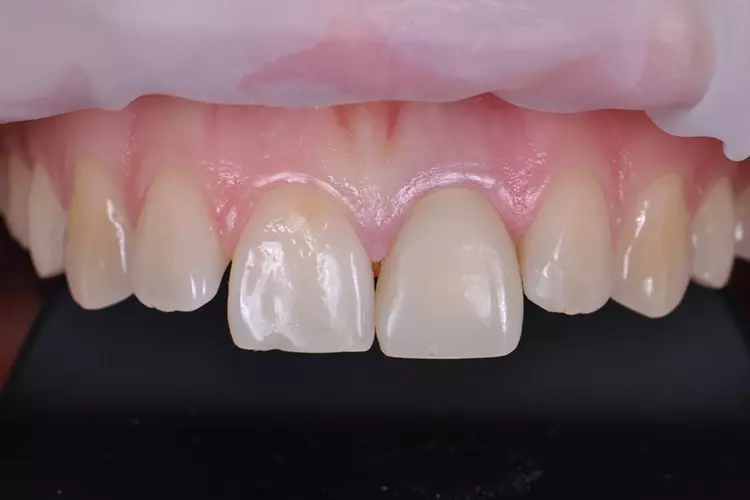

Zur Realisierung eines möglichst naturgetreuen Behandlungsergebnisses wurde labial ein minimales Cut-back und eine anschließende individuelle Schichtung mit der Verblendkeramik IPS e.max Ceram durchgeführt (Mikroveneering) (Abb. 30–33). Damit der verfärbte Zahnstumpf unter der neuen Zirkonkrone nicht mehr sichtbar ist, wird bei transluzentem Zirkoniumdioxid im Weißzustand auf der Innenseite des Gerüstes ein Opakerliquid aufgebracht. Dieses Liquid trägt nicht auf, da das Material in den Werkstoff eindringt und das Zirkongerüst an den gewünschten Stellen von innen blickdicht, sprich opak, wirken lässt (Fa. BriegelDental) (Abb. 34 und 35).

Die Innenseite der Restauration wurde vom zahntechnischen Labor vorbehandelt angeliefert. Das Provisorium wurde entfernt und die Stumpfreinigung wurde mit einer fluoridfreien Polierpaste (Proxyt) und einer Polierbürste durchgeführt. Bei der Einprobe der fertiggestellten Restauration wurden verschiedene Parameter wie Passgenauigkeit, approximale und okklusale Kontaktareale, Funktionsbewegungen sowie Oberflächentextur und Lichtreflexionen beurteilt.

Diese Maßnahme verhindert ein Abfließen des Befestigungsmaterials in den Sulkus. Nach der Einprobe wurde die Innenseite der Restauration gründlich mit Wasser abgespült und für 20 sec. mit Ivoclean – einer universalen Reinigungspaste – benetzt, um die Klebefläche nach der Kontamination mit Speichel zu reinigen (Abb. 37a und b). Anschließend wurde die Klebefläche der Restauration getrocknet und der selbstadhäsive Kompositwerkstoff (Speedcem Plus) appliziert.